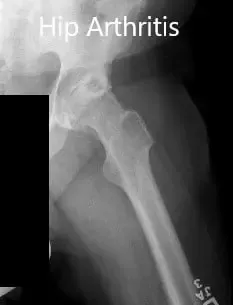

Los estudios de imagen revelaron osteoartritis bilateral severa de las caderas con quistes subcondrales, esclerosis y osteófitos. Teniendo en cuenta el dolor de cadera que limita el estilo de vida, le recomendaron una prótesis total bilateral. Ella aceptó seguir adelante con el procedimiento.

Radiografía preoperatoria que muestra las vistas laterales de la pata de rana de la articulación derecha e izquierda de la cadera.